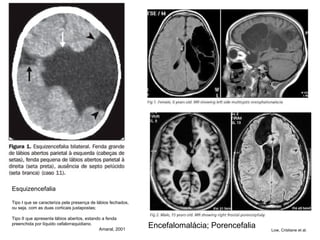

Esquizencefalia Tipo I que se caracteriza pela presença de lábios fechados, ou seja, com as duas corticais justapostas;  Tipo II que apresenta lábios abertos, estando a fenda preenchida por líquido cefalorraquidiano.  Amaral, 2001  Encefalomalácia; Porencefalia Low, Cristiane et al.

Esquizencefalia Esquizencefalia de lábios abertos (fenda longitudinal no hemisfério cerebral) E, com polimicrogiria heterotopias de substância cinzenta na porção profunda da fenda. Ausência do septo pelúcido. Tronco e cerebelo de morfologia normal.  Obs:  As malformações decorrem de lesão cerebral, geralmente de origem vascular, na fase de proliferação/migração (13ª a 24ª semanas de gestação). As heterotopias de substância cinzenta na porção profunda da fenda correspondem a neurônios que não migraram porque houve destruição das células da glia que guiam a migração. Não se trata de deficiência do processo de migração. O que houve foi a destruição do caminho que os neurônios seguiriam para formar o córtex.   Neuroimagem – Estudo de casos http://anatpat.unicamp.br/rpgneominis.html   caracteriza-se por fendas, que se estendem da superfície pial até a ependimária com as bordas revestidas por substância cinzenta.

Esquizencefalia Tipo Ique se caracteriza pela presença de lábios fechados, ou seja, com as duas corticais justapostas; Tipo II que apresenta lábios abertos, estando a fenda preenchida por líquido cefalorraquidiano. Amaral, 2001 Encefalomalácia; Porencefalia Low, Cristiane et al.

Esquizencefalia Esquizencefalia delábios abertos (fenda longitudinal no hemisfério cerebral) E, com polimicrogiria heterotopias de substância cinzenta na porção profunda da fenda. Ausência do septo pelúcido. Tronco e cerebelo de morfologia normal. Obs: As malformações decorrem de lesão cerebral, geralmente de origem vascular, na fase de proliferação/migração (13ª a 24ª semanas de gestação). As heterotopias de substância cinzenta na porção profunda da fenda correspondem a neurônios que não migraram porque houve destruição das células da glia que guiam a migração. Não se trata de deficiência do processo de migração. O que houve foi a destruição do caminho que os neurônios seguiriam para formar o córtex. Neuroimagem – Estudo de casos http://anatpat.unicamp.br/rpgneominis.html caracteriza-se por fendas, que se estendem da superfície pial até a ependimária com as bordas revestidas por substância cinzenta.